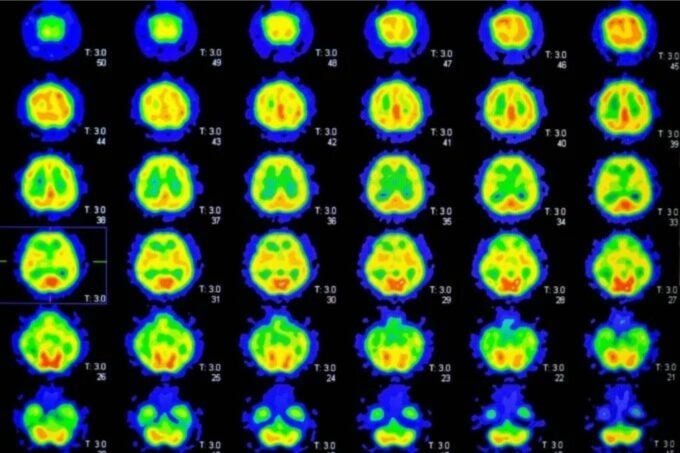

El Alzheimer es la forma más común de deterioro cognitivo, afectando actualmente a más de 7 millones de personas en Estados Unidos. Aunque sigue habiendo debate sobre su origen, una característica clave es la acumulación de placas de beta-amiloide en el cerebro. Esta acumulación puede comenzar años o incluso décadas antes de que aparezcan los primeros síntomas de la enfermedad. El PET es una herramienta útil para detectar esta acumulación, aunque no confirma si alguien desarrollará Alzheimer, pero sí puede descartar esta posibilidad a corto plazo.

Investigadores de Israel y Estados Unidos realizaron un seguimiento de cientos de personas antes y después de someterse a una Tomografía por Emisión de Positrones (PET) para evaluar su riesgo de padecer Alzheimer. Independientemente de si los resultados indicaban un alto o bajo riesgo, la salud mental de los participantes se mantuvo estable. Sin embargo, el estudio reveló que las personas se volvieron menos motivadas a mantener hábitos saludables que podrían reducir su riesgo de sufrir deterioro cognitivo.